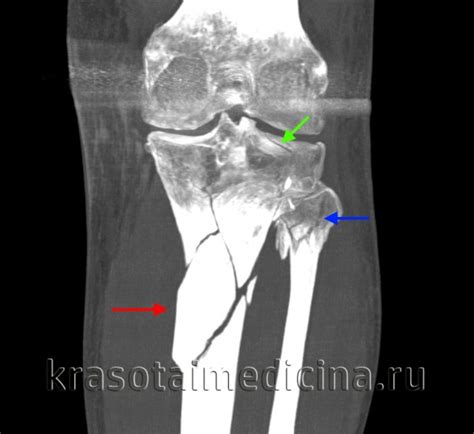

Перелом голени - причины, симптомы, диагностика...

Кости голени: наименования, расположение, грани...